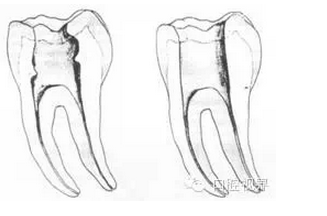

左圖為正常開(kāi)髓孔的大小和位置。左邊圖為下顎,右邊圖為上顎。